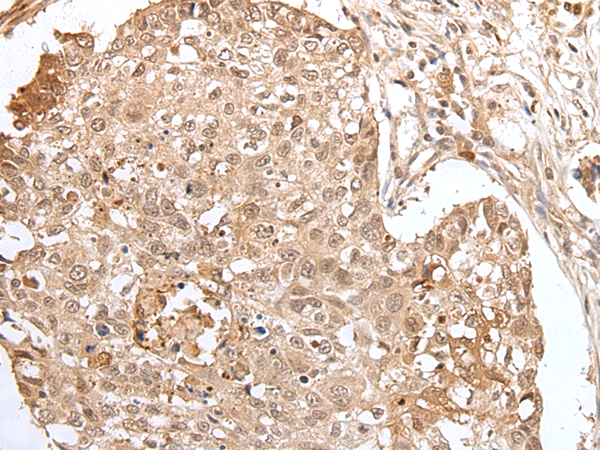

Applications:

ELISA, IHC

IHC positive control:

Human lung cancer

IHC Recommend dilution:

25-100